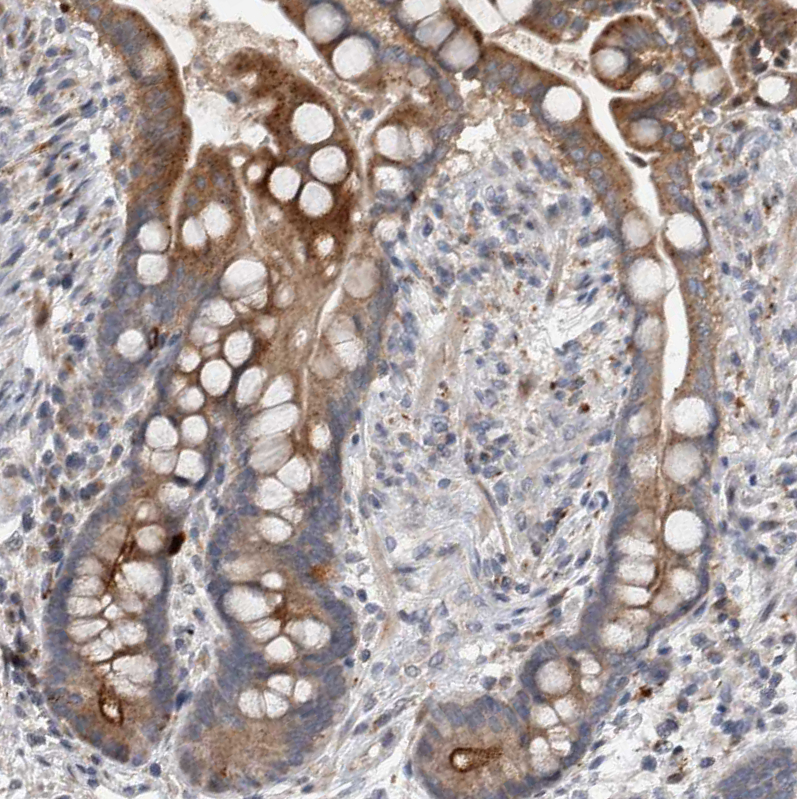

Immunohistochemistry analysis in human skin and skeletal muscle tissues using HPA023369 antibody. Corresponding FAM83G RNA-seq data are presented for the same tissues.